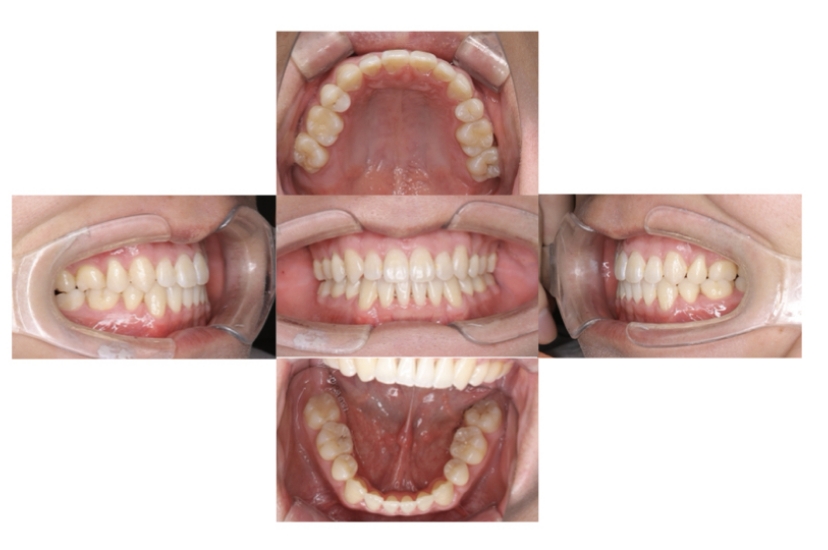

AFTER

上下顎叢生、上顎前突(出っ歯、上下の前歯のガタガタ)のケースです。

装置はラビアル(上下表側)で、上顎の小臼歯を2本抜歯を行っています。抜歯したスペースを使って、上の前歯の後方移動と叢生(ガタガタ)と出っ歯の改善を行っています。下は歯と歯の間にIPR(隣接面削合)を行い、スペースを確保し、叢生の改善を行っています。

主訴 前歯のガタガタと出っ歯が気になる。

年齢・性別 47歳 女性

お住まいの地域 神奈川県川崎市

治療方針 抜歯スペースおよびIPRを利用して上前歯の叢生(ガタガタ)の改善

抜歯部位 上顎左右第一小臼歯

使用装置 ラビアル(上下表側)、顎間ゴム

治療期間 2年0か月

治療回数 15回

リテーナー クリアリテーナー